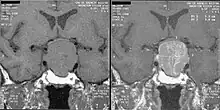

Diagnosis

If acromegaly is suspected, medical laboratory investigations followed by medical imaging , if the lab tests are positive, confirms or rules out the presence of this condition.

An MRI of the brain focusing on the sella turcica after gadolinium administration allows for clear delineation of the pituitary and the hypothalamus and the location of the tumor. A number of other overgrowth syndromes can result in similar problems.